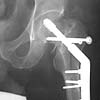

Attached here few x-rays of a multi-trauma patient. He is a 51years old man,sustain MVA at 08/15/99 and refer to our hospital few days ago, more than twoweeks after injury. He sustain Bilateral femoral fracture including femoralneck, A right humerus fracture, right distal radius fx, left open ulnar fx,right tibial plateau (type III) fx and Chopart fracture dislocation of the rightfoot. At the other hospital where he was admitted, He underwent laparotomy andfixation of both femur by reconstruction IMN, application of Ex Fix to thehumerus, and reduction and K.W. fixation of the Rt foot. He is currently stable and conscious. He is scheduled next week for replacing of the Rt IMN to aretrograde nail and pinning (6.5 mm screws) of the neck fracture, fixation ofthe ulna, distal radius and tibial plateau.

AP Pelvis

Lt femur

Rt femur